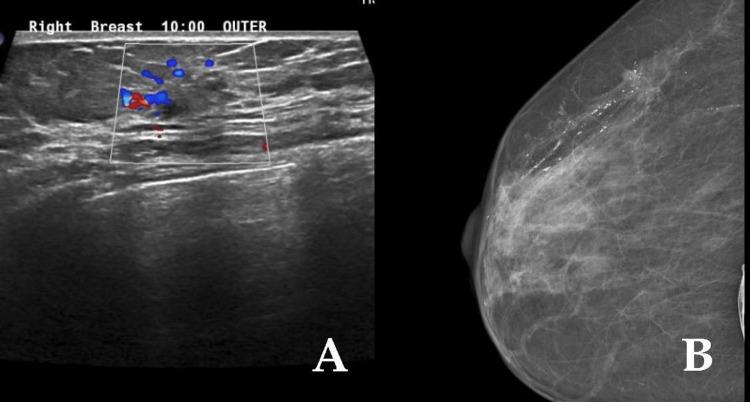

Multiple primary malignant tumors (MPMT) can be defined as more than two different tumors synchronously or metachronously forming in the same organ or different organs. The incidence of MPMTs varies dramatically between antemortem and postmortem examinations, becoming a serious medical issue. Evidence shows that the overall incidence of MPMTs is between 2.4% and 17%. Double primary malignancy (DPM) is considered the most common type of MPMT. In this case series, we present three cases of MPMT. The first case involved the colon and the breast, the second case involved the colon and the kidney, and the third case involved rectum and kidney.

多原发性恶性肿瘤(MPMT)可定义为在同一器官或不同器官中同步或异时形成的两种以上不同肿瘤。MPMT的发病率在生前检查和死后检查之间差异很大,成为一个严重的医学问题。证据表明,MPMT的总体发病率在2.4%至17%之间。双原发性恶性肿瘤(DPM)被认为是MPMT最常见的类型。在本病例系列中,我们呈现了3例MPMT病例。第一例涉及结肠和乳腺,第二例涉及结肠和肾脏,第三例涉及直肠和肾脏。